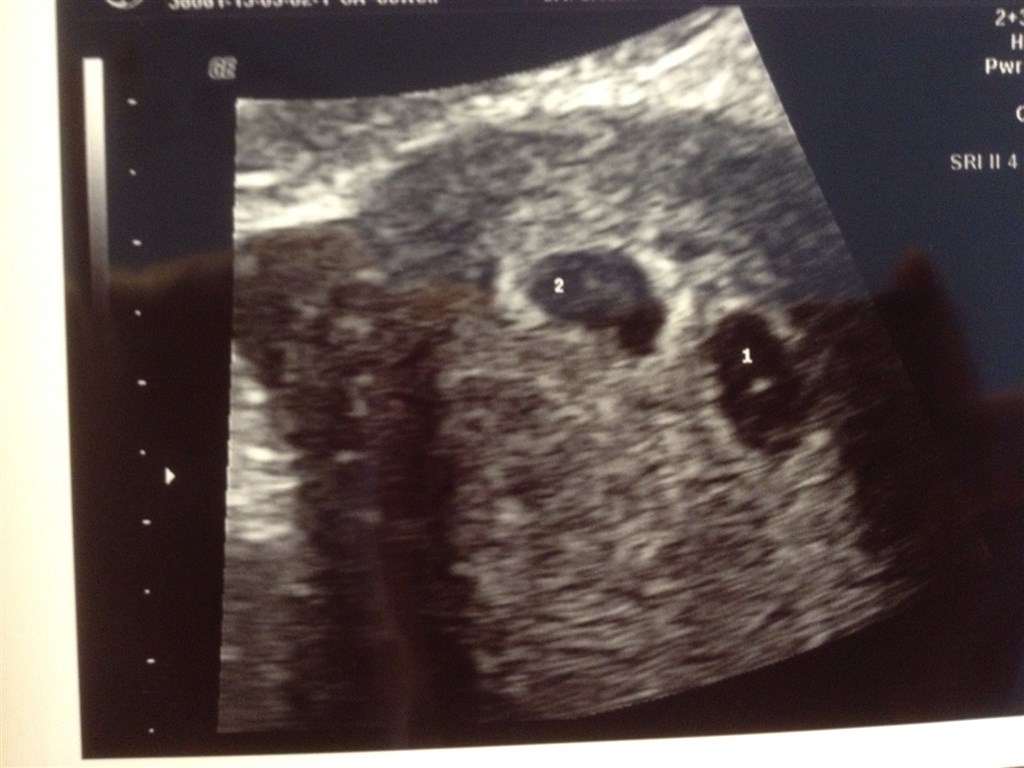

Det her er resultatet efter at have fået lagt to æg op i et friskt ICSI forsøg... ❤❤❤❤❤❤❤

Hov glemte billedet...

Hvor fint, Tillykke, håber vi bliver lige så heldige